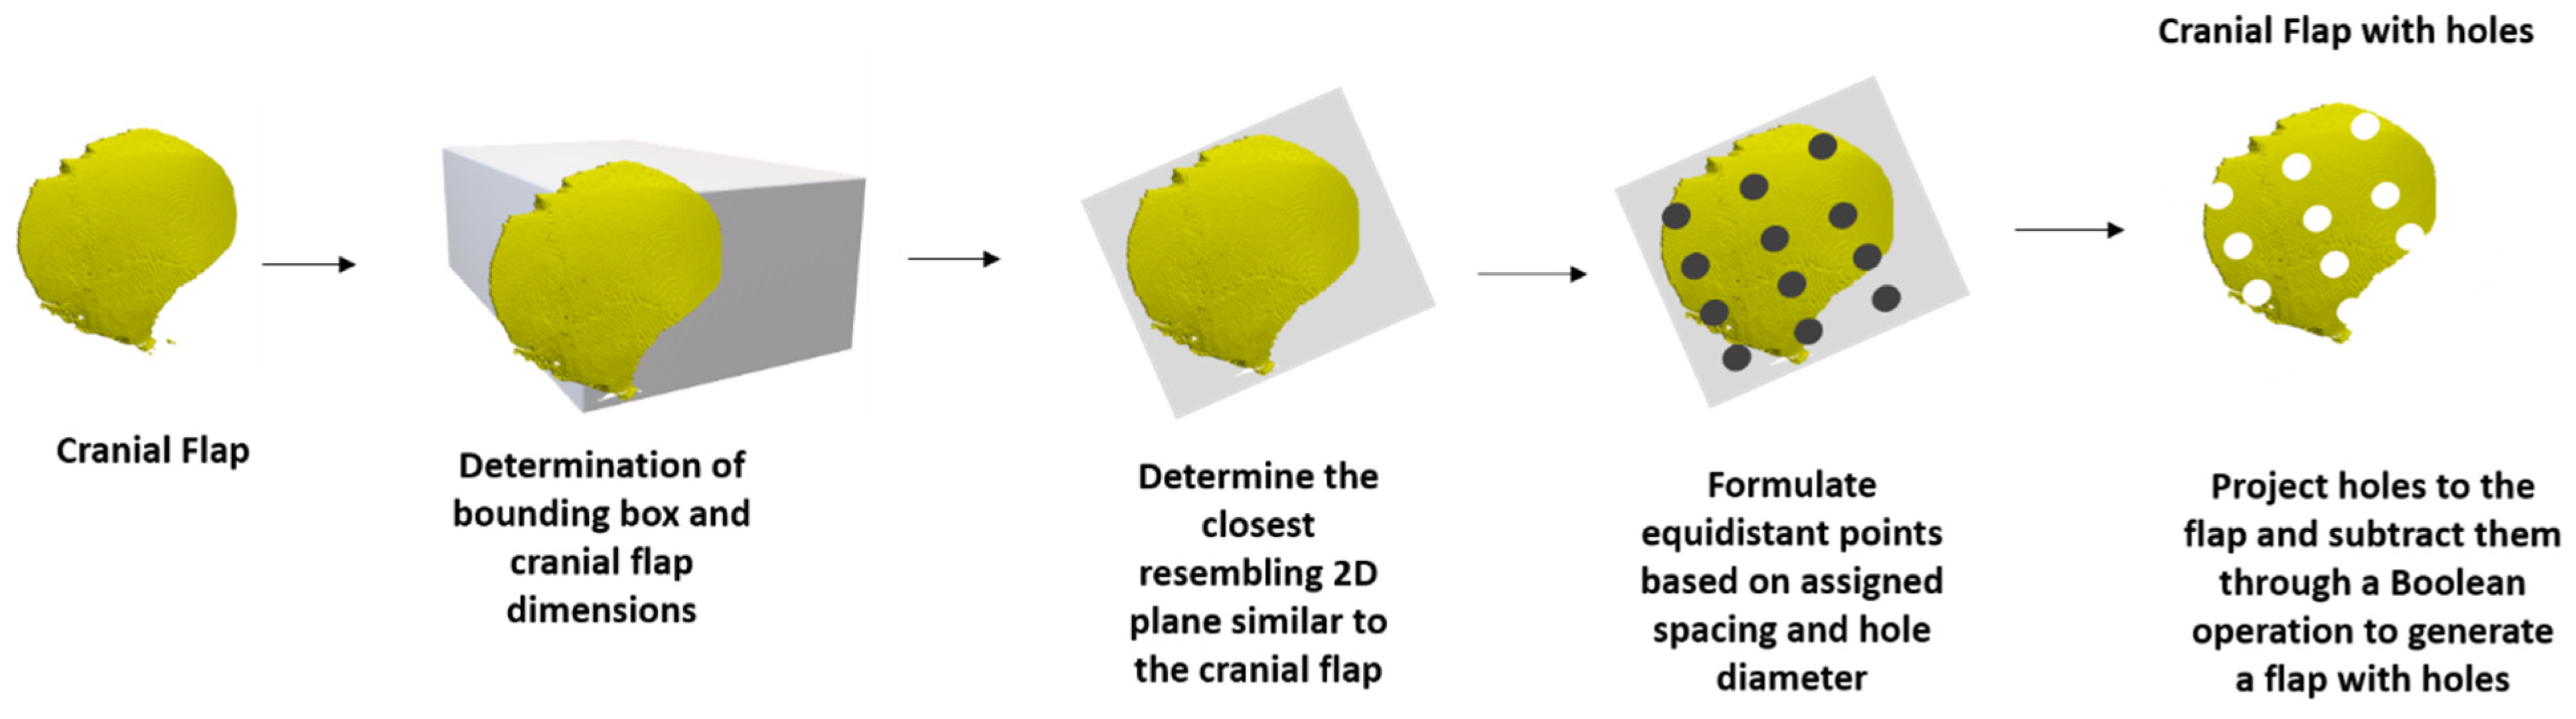

2. Materials and Methods

3. Results

3.2. Feedback from the Ukrainian Team

| Add the detail of including a grid of outlet holes onto the designed implant. | Effort required to address: High. Ability to improve software: Valuable as it is more in line with current clinically used implants and would allow future users the option of directly printing implants rather than molds. | 4 |